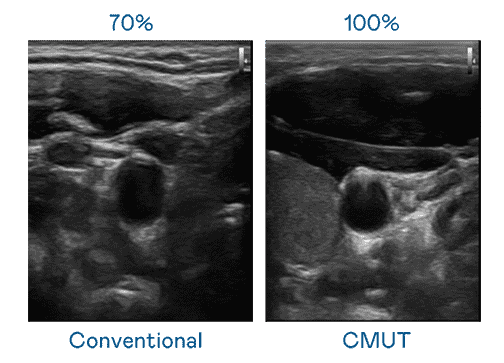

CMUT 技术是一种用电容式微机电元件来产生超音波讯号的技术。。与传统 PZT 压电式技术相比,,,,CMUT 频宽增加 30%,,更宽频的超音波讯号让影像解析度大幅提升,,是实现高影像品质医疗超音波扫描、、、促进精准医疗发展的关键技术。。。。

大频宽带来超清晰影像

超音波影像的解析度高低,,,首先取决于探头能发出的讯号频宽。。。z6mg·人生就是博 CMUT 可提供高清晰的超音波讯号,,提供高频宽、、、高灵敏度、、、、影像纹理细节更高的超音波影像,,协助医护人员缩短影像判读时间及利用精准的医疗影像进行诊断。。